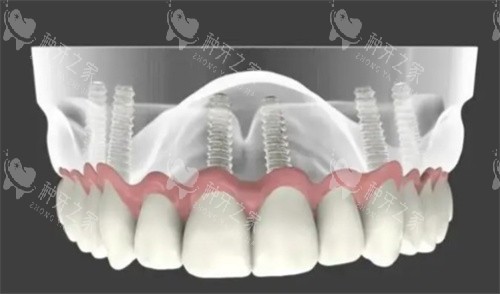

all-on-4全口种植牙模型图

全口种植牙解析图

全口种植牙的示意图